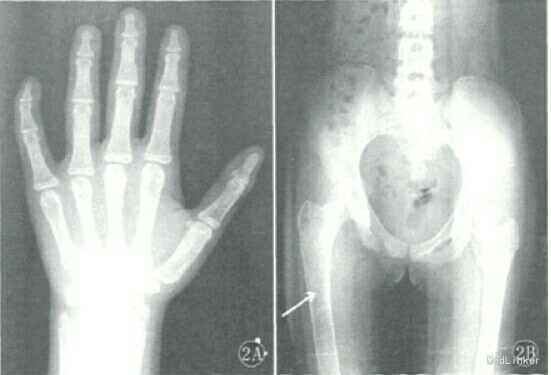

体检发现头颅前后径增大,枕骨后突;双侧上臂略增粗。皮肤未见色素沉着。 超声检查可见甲状腺散在钙化点。血清学检查T3、T4轻度增高。患儿5岁时拍摄腕骨正位片(图1A),发现掌指骨密度减低;骨质稀疏;腕骨出现7枚骨化中心;所有远节指骨骨化中心与骨干基本等宽,骨龄相当于8~9岁男孩标准。双侧上臂正位片显示(图1B),双侧肱骨膨胀,骨皮质变薄,髓 腔内可见磨玻璃样、丝瓜瓤样改变以及囊状骨质破坏;骨骺未受累;右侧尺骨鹰嘴町见斑片状骨质硬化。头颅MRI显示(图1C),枕骨膨胀性改变,颅板变薄,板障增宽;枕骨右侧可见黄豆大小囊性T:高信号区;左侧乳突未气化,向外突出,其内可见不均匀异常信号。

诊断:McCune--Albright综合征